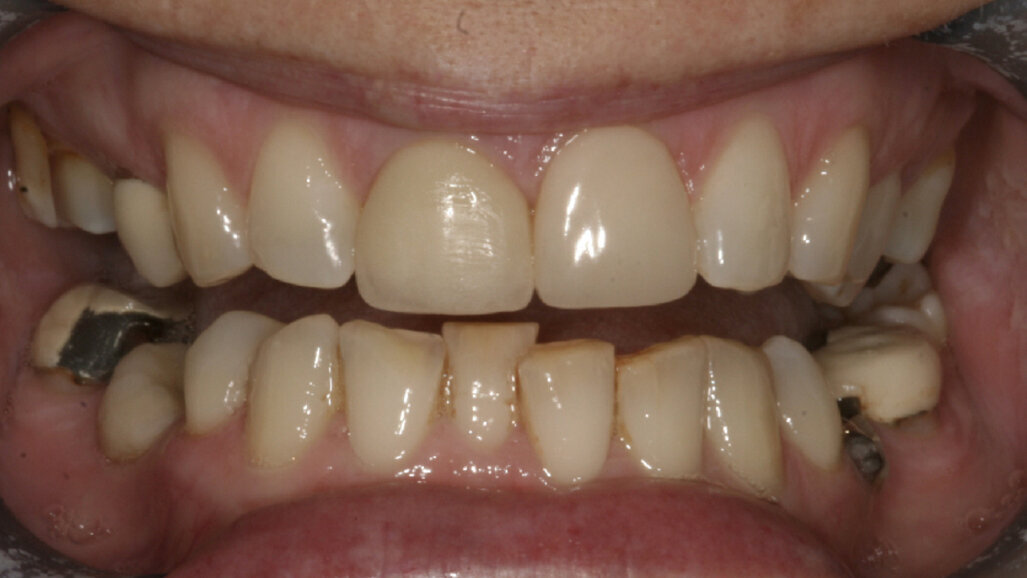

A 48-year-old female patient came to see me in 2004. The patient initially presented because she was unhappy with her two discoloured maxillary central incisors (Fig. 1). She also had chipping and wear of the mandibular teeth and broken posterior bridgework. Her “bite” also felt uncomfortable (Fig. 2).

On examination, she had reduced anterior guidance, causing posterior interferences and heavy contacts behind the maxillary central incisors. The patient was keen to change the crown and veneer on the maxillary central incisors. She also wanted to have the wear on her mandibular teeth and the crowding treated (Fig. 3).

Fig. 2: 2004—reduced anterior guidance.

Fig. 3: 2004—wear on the mandibular teeth and crowding.